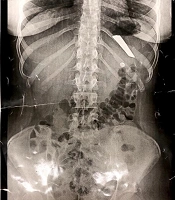

Repeated Intentional Swallowing of Foreign Objects by an Adolescent Girl (Case Report)

Parisa DivsalarORCID*,

Soudabehsadat Hosseini Mousa,

Mehdi Hayatbakhsh Abbasi